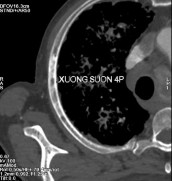

- Nhiều tổn thương di căn lan toả nhu mô 2 phổi kèm theo lớp dịch

mỏng màng phổi 2 bên.

- Di căn hạch trung thất, hạch sau phúc mạc.

- Nhiều ổ đặc xương thứ phát ở xương sườn 4 phải, xương sườn 8 trái và nhiều đốt sống (thấy rõ ở D12, L2, L5).

Hình C. Hình ảnh chụp CT tại thời điểm kháng cắt tinh hoàn